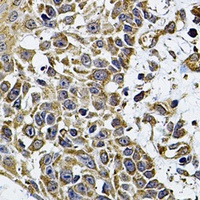

CD275 Antibody抗体

CD275 Antibody

IHC, WB

Rabbit

Human, Mouse, Rat

Recombinant fusion protein of human CD275

免疫原:Recombinant fusion protein of human CD275

应用稀释比例:WB: 1:500-2000

纯化:The antibody was purified by immunogen affinity chromatography.